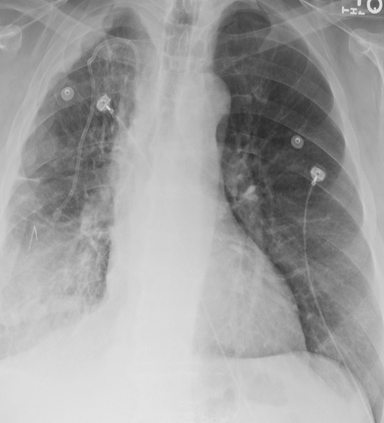

Tuberculosis remains a critical global health issue, particularly in resource-limited and remote areas. Early detection is vital for treatment, yet the lack of skilled radiologists underscores the need for artificial intelligence (AI)-driven screening tools. Developing reliable AI models is challenging due to the necessity for large, high-quality datasets, which are costly to obtain. To tackle this, we propose a teacher--student framework which enhances both disease and symptom detection on chest X-rays by integrating two supervised heads and a self-supervised head. Our model achieves an accuracy of 98.85% for distinguishing between COVID-19, tuberculosis, and normal cases, and a macro-F1 score of 90.09% for multilabel symptom detection, significantly outperforming baselines. The explainability assessments also show the model bases its predictions on relevant anatomical features, demonstrating promise for deployment in clinical screening and triage settings.